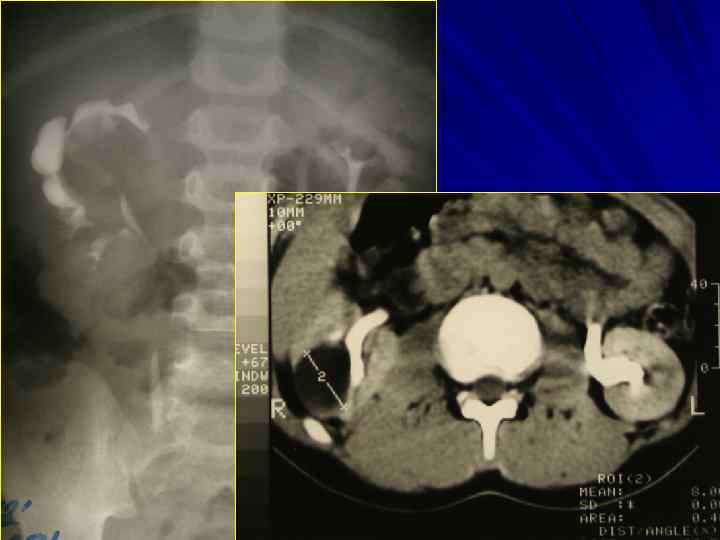

АНОМАЛИИ РАЗВИТИЯ МОЧЕПОЛОВОЙ СИСТЕМЫ

Сосудистая ножка почки